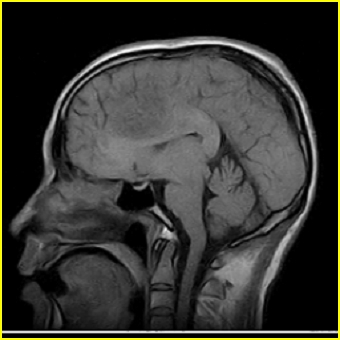

男,45岁,头部剧烈疼痛伴呕吐5天。

右侧额叶见较大的类圆形长t1信号环绕等t1环影,长t2信号环绕短等t2环,周围见明显水肿占位征,中线结构左移,男,45岁,头部剧烈疼痛伴呕吐5天。

右侧额叶,见一占位病灶,t1像病灶、水肿长t1;其间为短t1环行信号。t2像病灶、水肿长t2,其间为短t2环行信号。占位效应明显,中线左移,右测脑室受压闭塞。结合患者发病较急。首先考虑:右侧额叶脑脓肿形成。鉴别:1、转移瘤,多发多见2、胶质瘤。建议增强

1、脑脓肿可能大 2、右上颌窦炎 3、建议增强